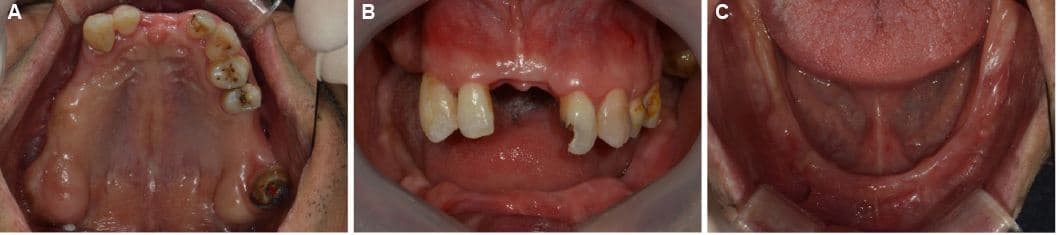

Comprehensive Treatment by Prosthodontist

Our prosthodontist optimally combines various treatments including implants, crowns, and bridges to create the best results at reasonable costs.

Full Mouth Reconstruction · Mr. S●● · Male, 70s

Full Mouth Reconstruction · Mr. O●● · Male, 60s

Front Teeth Implant · Ms. K●● · Female, 50s

Front Teeth Implant · Mr. L●● · Male, 60s

Molar Implant · Mr. P●● · Male, 50s